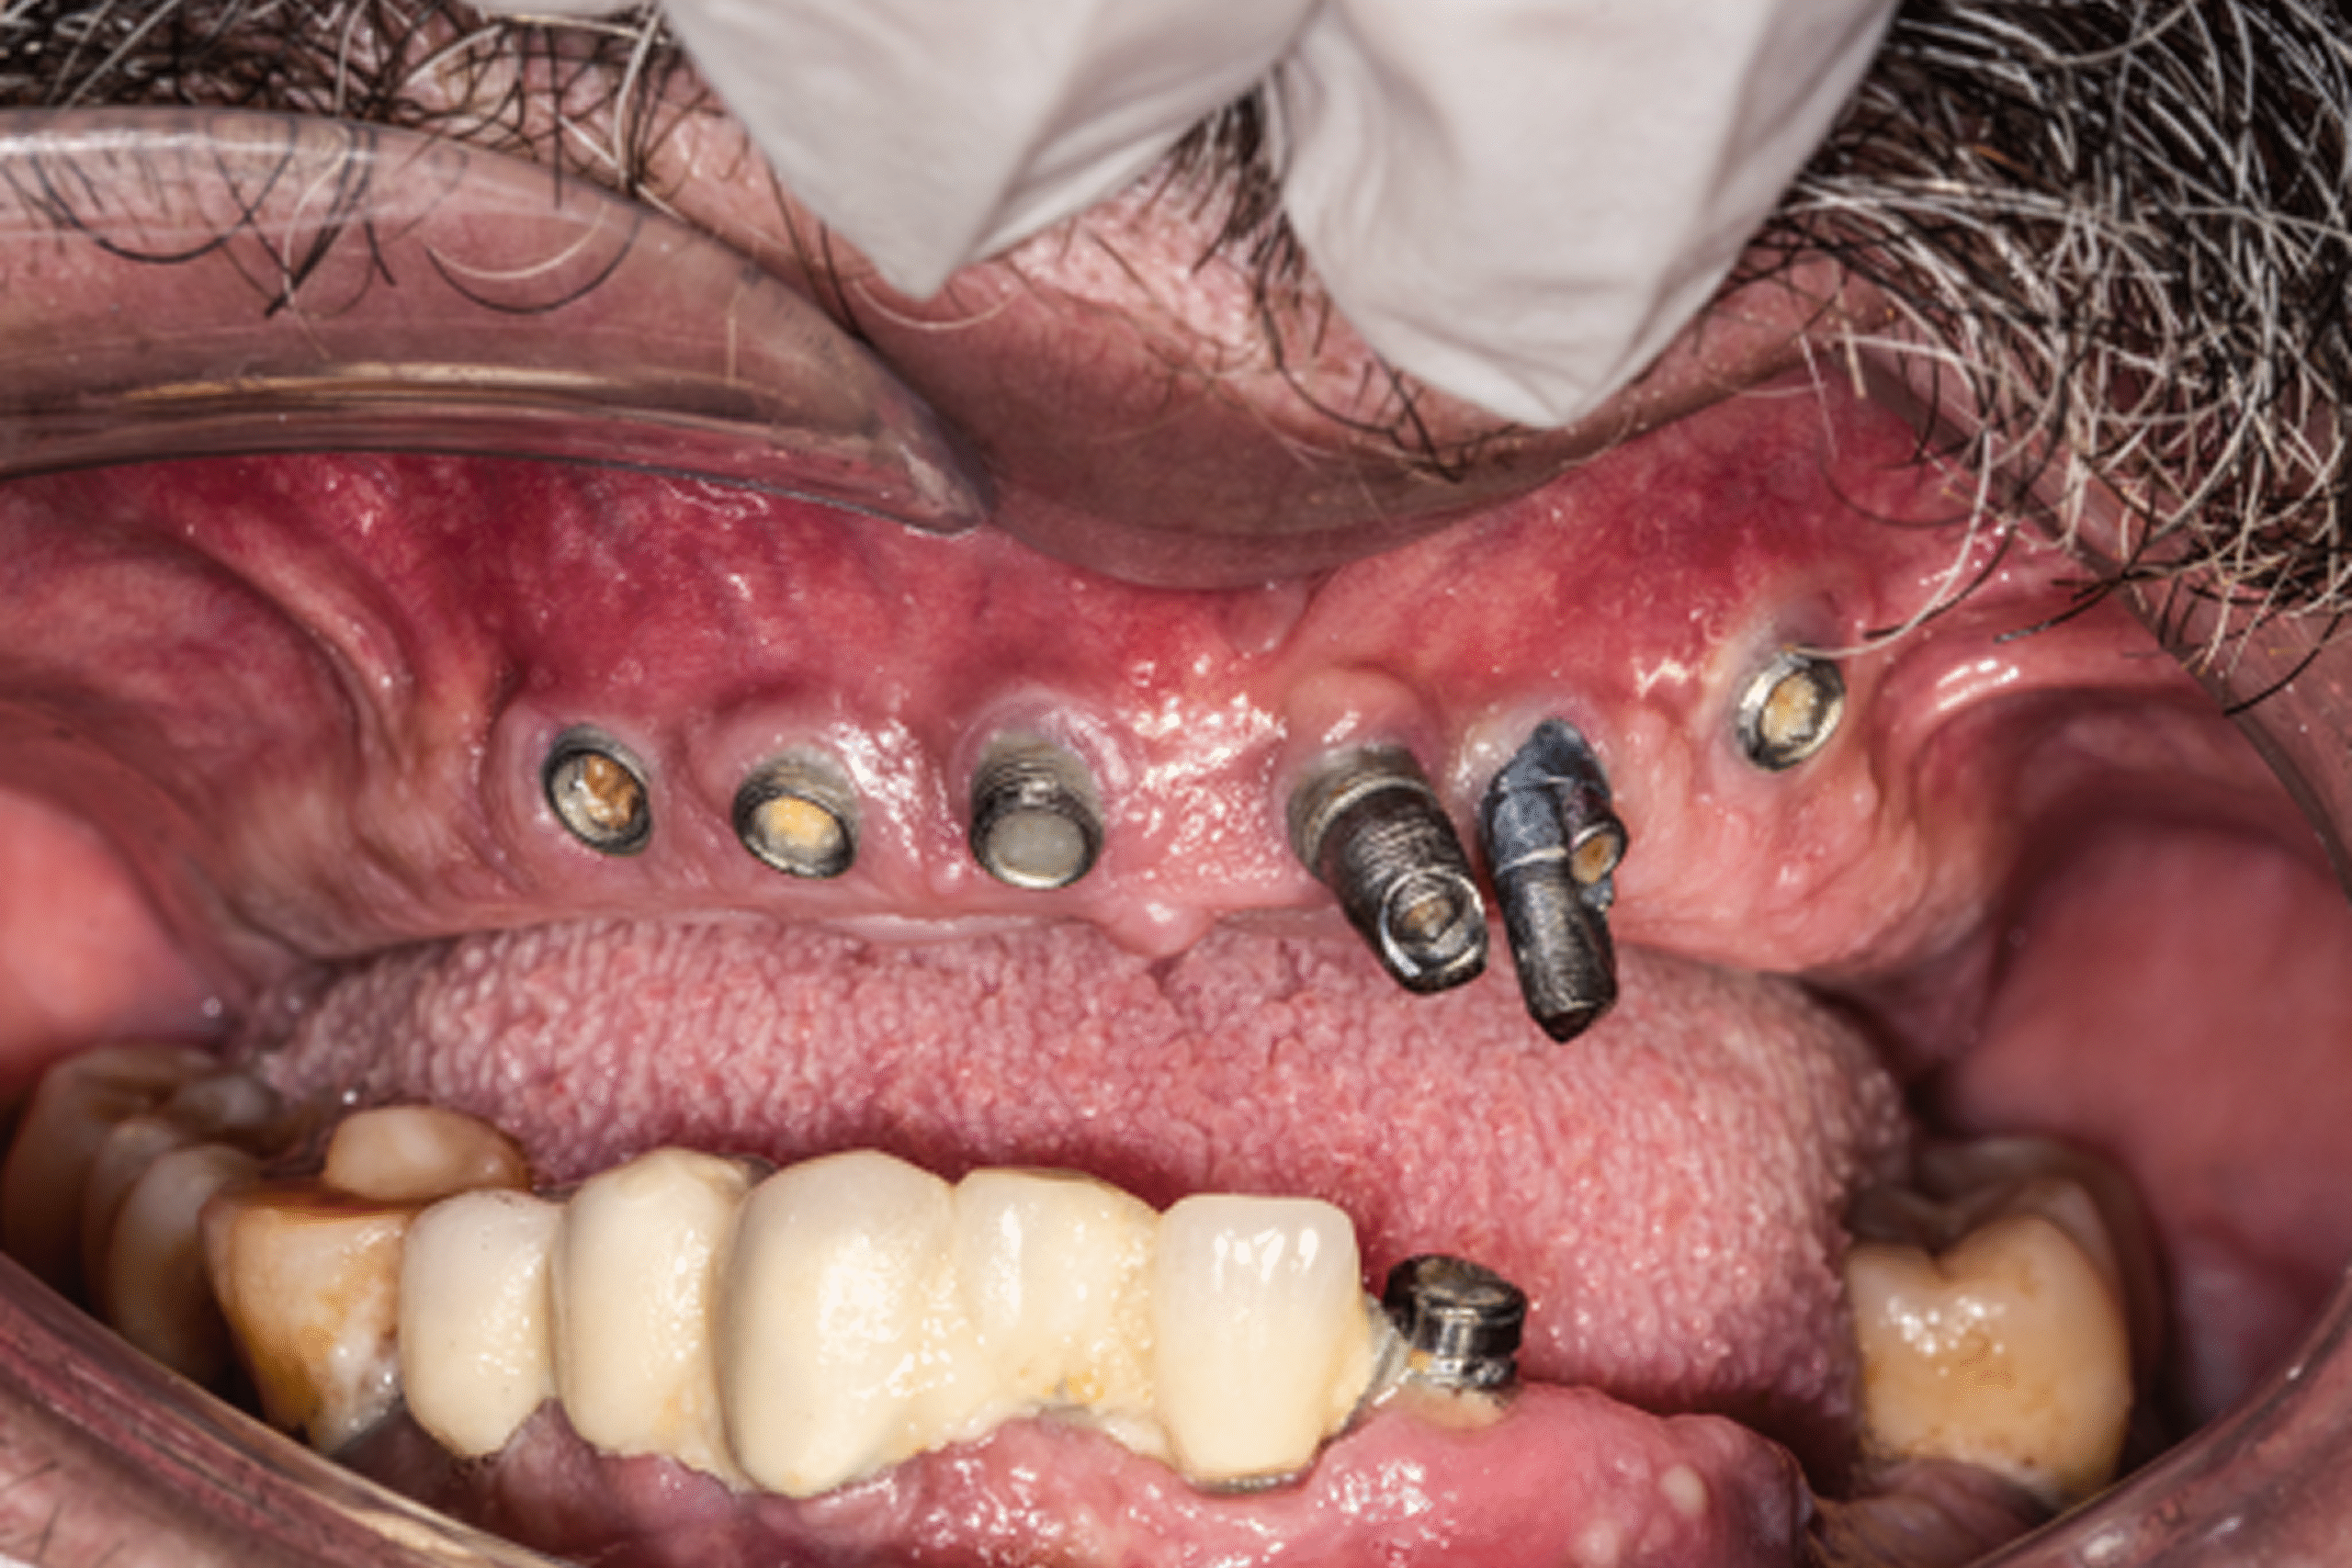

Daniel Wright arrived at our clinic after experiencing a severely compromised outcome from previous implant treatment performed elsewhere. His earlier procedure involved poorly placed implants, no comprehensive treatment plan, and a lack of proper prosthetic vision, ultimately leading to functional failure, discomfort, and a deteriorating oral condition.

Recognizing the complexity of his situation, our team conducted a full diagnostic assessment, including detailed clinical evaluation and advanced 3D imaging. The findings confirmed that the existing implants were unsalvageable due to incorrect angulation, inadequate support zones, and prosthetic misalignment.

Day 2 — Surgical Phase

- Removal of all improperly placed implants

- Placement of four strategically positioned implants (All-on-4)

- Guided surgery ensured optimal distribution, angulation, and stability